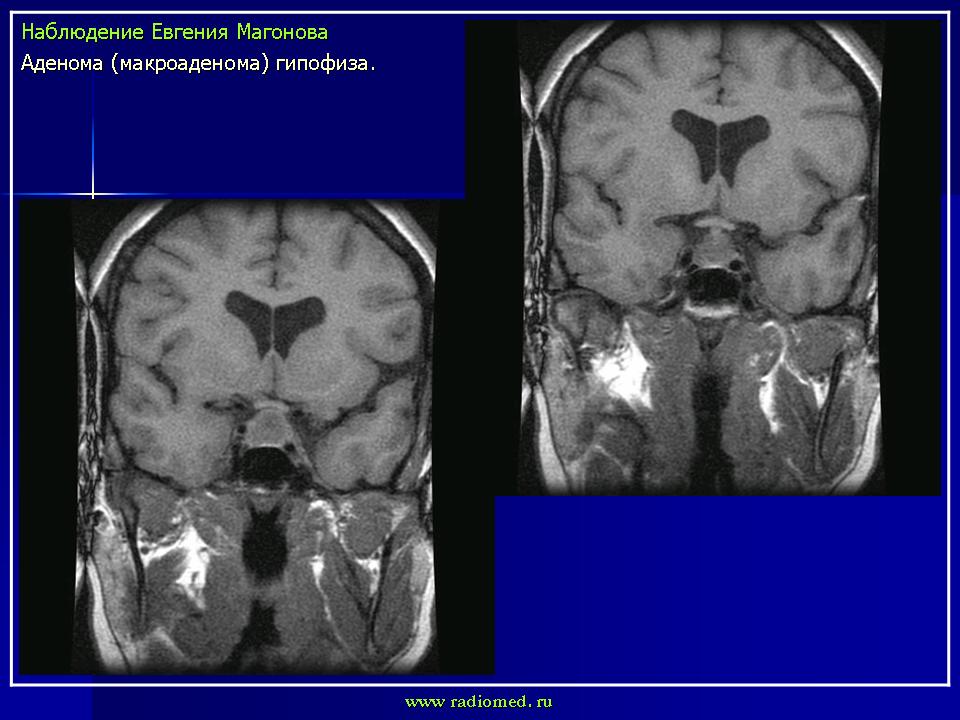

впервые настолько глубокие изменеия турецкого седла, что даже не требуется дообследование.

adenoma_gipofiza_1.jpg